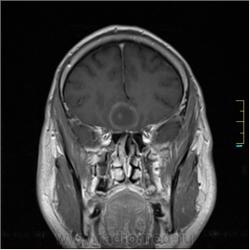

Пациентка направлена на исследование с диагнозом "Гипертонический криз", энцефалопатия неуточненная.

Cor T1:

частично функционирующая аневризма

Иначе говоря, аневризма с хронической геморрагией, т.к. мы видим фракции крови различного возраста.

По-моему, аневризма с пристеночными тромбами.

Постепенное пристеночное образование тромбов приводит к появлению типичного для аневризмы феномена -слоистости МР сигнала в полости аневризмы. Данная картина демонстрирует слоистый характер тромботических масс в полости аневризмы .Функционрирующая часть имеет низкий сигнал во всех режимах сканирования. Дополнительно-перифокальный отек.

А может более корректно интерпретировать как частично тромбированная аневризма... Уж коь речь идет о фракциях, ну то есть о тромбе по сути.... Ну и плюс перфокальный отек головного мозга (вероятнее цитотоксический+вазогенный).